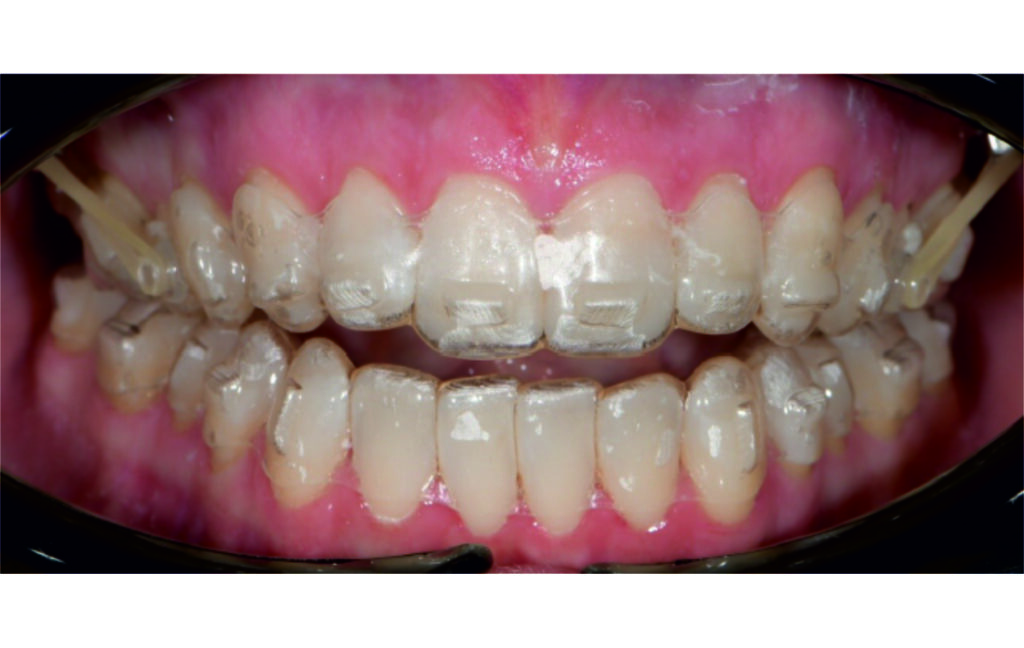

A 1.5 mm deviation of the upper dental midline to the patient’s left was noted, along with a slight mandibular midline shift to the right, likely due to asymmetrical mandibular growth observed in the facial structure. Severe mesial rotations of teeth 16 and 26 were evident in the initial records. As derotation of 16, 26, 17, and 27 progressed up to aligner 16, the premolars in segments I and II moved distally, resulting in a bilateral Class I relationship, as intended in the initial treatment plan.

Derotation of 16 26 allowed Class II correction.

Vertical vector of elastic traction on buttons and IZC helped with the open bite correction.

No sequential distalization for Class II tendency correction was performed due to skeletal anchorage. Lingual attachments were used to improve aligner grip and control tooth movement, as small, angulated lower incisors are difficult to move due to limited anatomy.